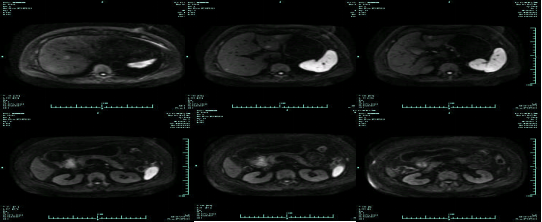

MR-H1

影像学检查结果评估:cPD。

疗效评估:cPR

TOGA研究是第一个使用HER2抑制剂曲妥珠单抗治疗不能手术的局部晚期、复发或转移的HER2阳性胃癌患者的Ⅲ期临床研究。TOGA研究结果显示,IHC2+/FISH阳性或者IHC3+的患者与对照组相比,OS分别为16.0个月和11.8个月(HR为0.65)。曲妥珠单抗联合化疗显著提高了HER2阳性晚期转移性胃癌的治疗缓解率和总体生存率。2012年8月,曲妥珠单抗治疗HER2阳性转移性胃癌适应症在我国获批。对该患者进行病理切片会诊,幸运的是其HER2检测为阳性。随即进行靶向联合化疗治疗,三个周期后,肝转移灶消失,曲妥珠单抗治疗效果显著。九个周期的靶向治疗联合放化疗后,疗效评估cPR,随即行手术治疗。